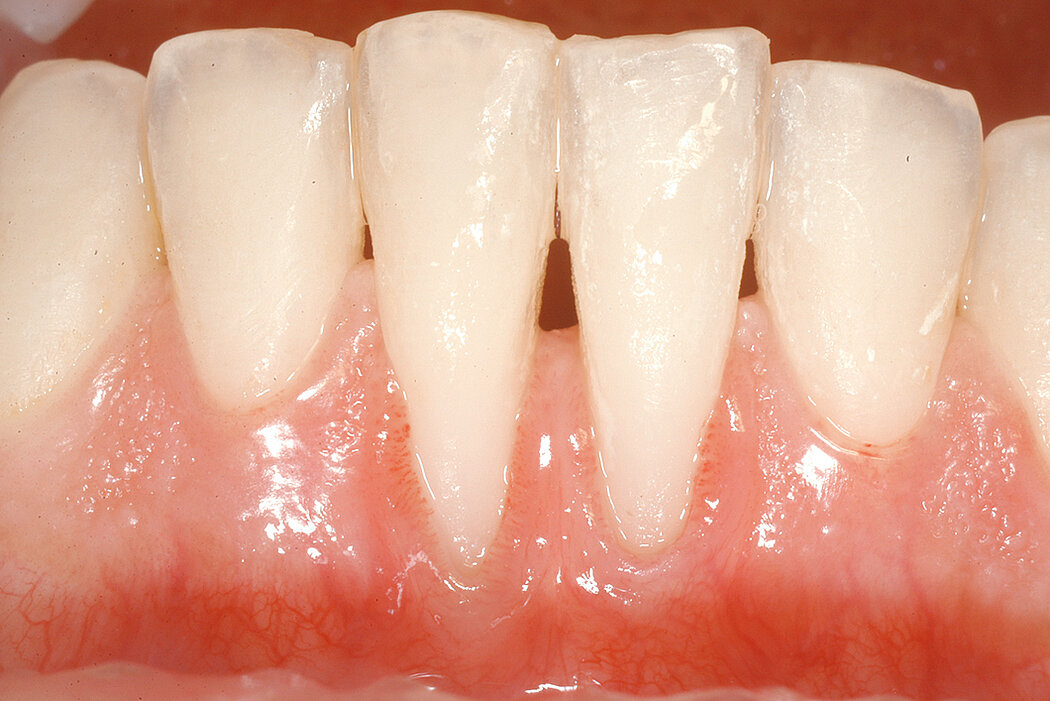

天然牙周围的角化组织增宽

目标

下颌前牙区增宽角化组织。

结论

在某些情况下,角化组织缺乏与刷牙、持续的牙龈炎症及肌肉牵拉引起的不适有关。此病例目的在于使用Geistlich Mucograft®来增宽下颌中切牙颊侧的角化组织,同时避免在上腭部取游离龈移植。最终结果,术后6月可见新增角化组织带良好协调的色泽与质地。手术效果达到患者预期,改善了刷牙不适的症状。在此阶段没有打算覆盖暴露的根面;不过,如需施行二期的根面覆盖手术,现有临床条件已经具备。